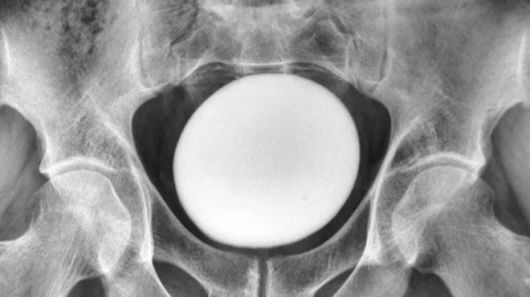

이 덩어리는 골반이나 복벽에 붙어있지 않았다. 초음파 검사 결과 지름 약 11㎝의 달걀 형태의 물체였다.

이란 35세 남성의 방광에서 발견된 타조알 크기의 결석. [라이브사이언스] |

의료진은 이를 비정상적으로 큰 방광 결석으로 진단했다. 결석은 소변 속 미네랄이 결정으로 쌓이면서 자라는데, 약 85%가 칼슘으로 이뤄져 있다.

의사들은 이 결석이 요로를 막거나 압박하지 않는지 확인한 뒤 수술로 제거했다. 꺼낸 결석은 무게 826g, 길이 약 13㎝, 너비 약 10㎝, 높이 약 8㎝였다. 이처럼 수술로 제거해야 하는 거대 결석은 “매우 드물다”고 보고서는 밝혔다.